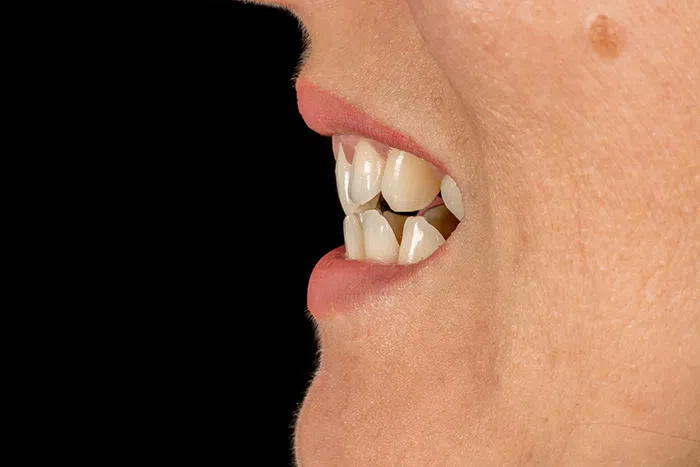

Caz estetică dentară – Coroane zirconiu ceramică – Hollywood Smile

Provocarea acestui caz a fost în egalarea și uniformizarea zâmbetului pacientului, acesta având multipli dinți asimetrici cât și corecția mușcăturii inverse în zona molarilor.

Pacientul nu a dorit aparat dentar. Ca material a fost folosit zirconiu ceramică, pentru o rezistență crescută, pacientul având bruxism (scrâșnit) dentar pronunțat. Pacientul a dorit un Hollywood Smile, însemnând o culoare mult mai deschisă decât a vechilor dinți, optând pentru o nuanță Bleach 2, dar și o formă cât mai netedă și perfectă a noilor coroane.

Pacientul a beneficiat de schimbarea obturațiilor vechi (plombe), tratamente de canal realizate la microscop, cât și de evaluarea problemelor parodontale.